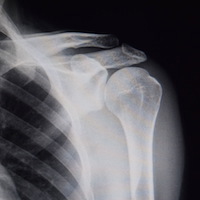

Unsere Ordination bietet rund um die Uhr kompetente Erstversorgung von frischen Unfällen und Verletzungen jeglicher Art an. Dabei sind ein digitales Röntgen sowie moderne Versorgungsmaterialien wie Kunststoffgips und speziell angepasstes Schienenmaterial natürlich inbegriffen.

Zudem wird eine unbürokratische Abwicklung der Administration und Organisation der gegebenenfalls Weiterversorgung inklusive erweiterter Bildgebung (CT, MRT) und zeitnaher operativer Versorgung garantiert.

Unfallversorgung rasch und unkompliziert.